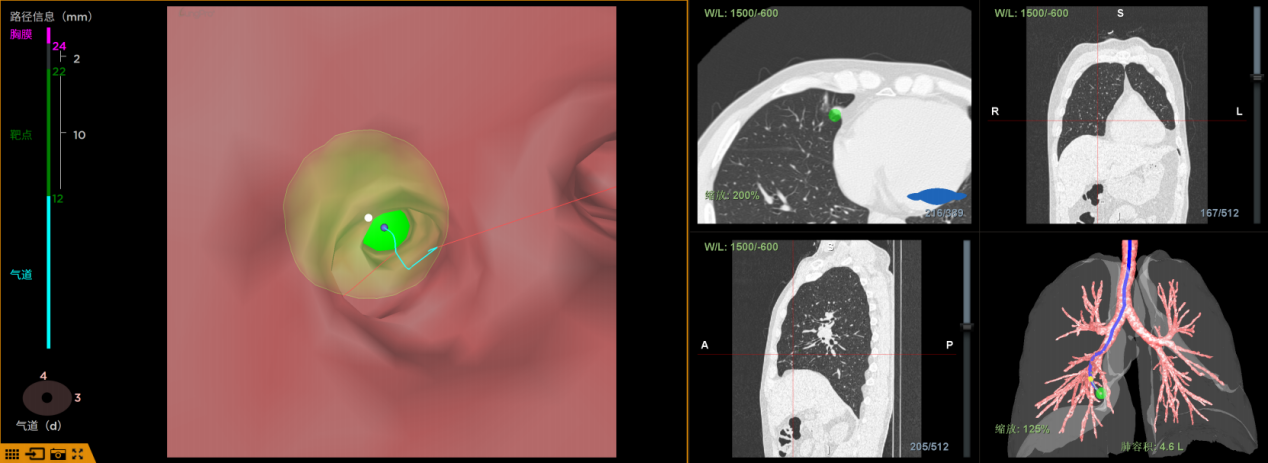

LungPro導航,即增強現實光學全肺診療導航,被譽為“肺內 GPS”,可根據患者CT數據,以1:1的比例重建全肺 3D 地圖,直觀且精準地呈現肺部結構與結節位置,并自動規劃出避開血管的最優手術路徑,其定位誤差控制在 1 毫米以內。有效攻克深部、微小、亞實性肺結節的定位難題,實現肺部手術“指哪打哪”的精準目標。

在傳統的肺部疾病診療中,針對緊鄰膈肌、心臟等重要部位的肺深部結節,采用傳統 CT 穿刺定位存在較高風險,不僅容易損傷周圍臟器,且治療費用相對昂貴。而 LungPro 導航通過自然氣道無創抵達病灶部位,無需使用額外耗材,具備低成本、零輻射、零血氣胸風險等顯著優勢,對直徑小于 10mm 的微小結節診斷率高達 96%,極大程度保障了患者的醫療安全與經濟利益。